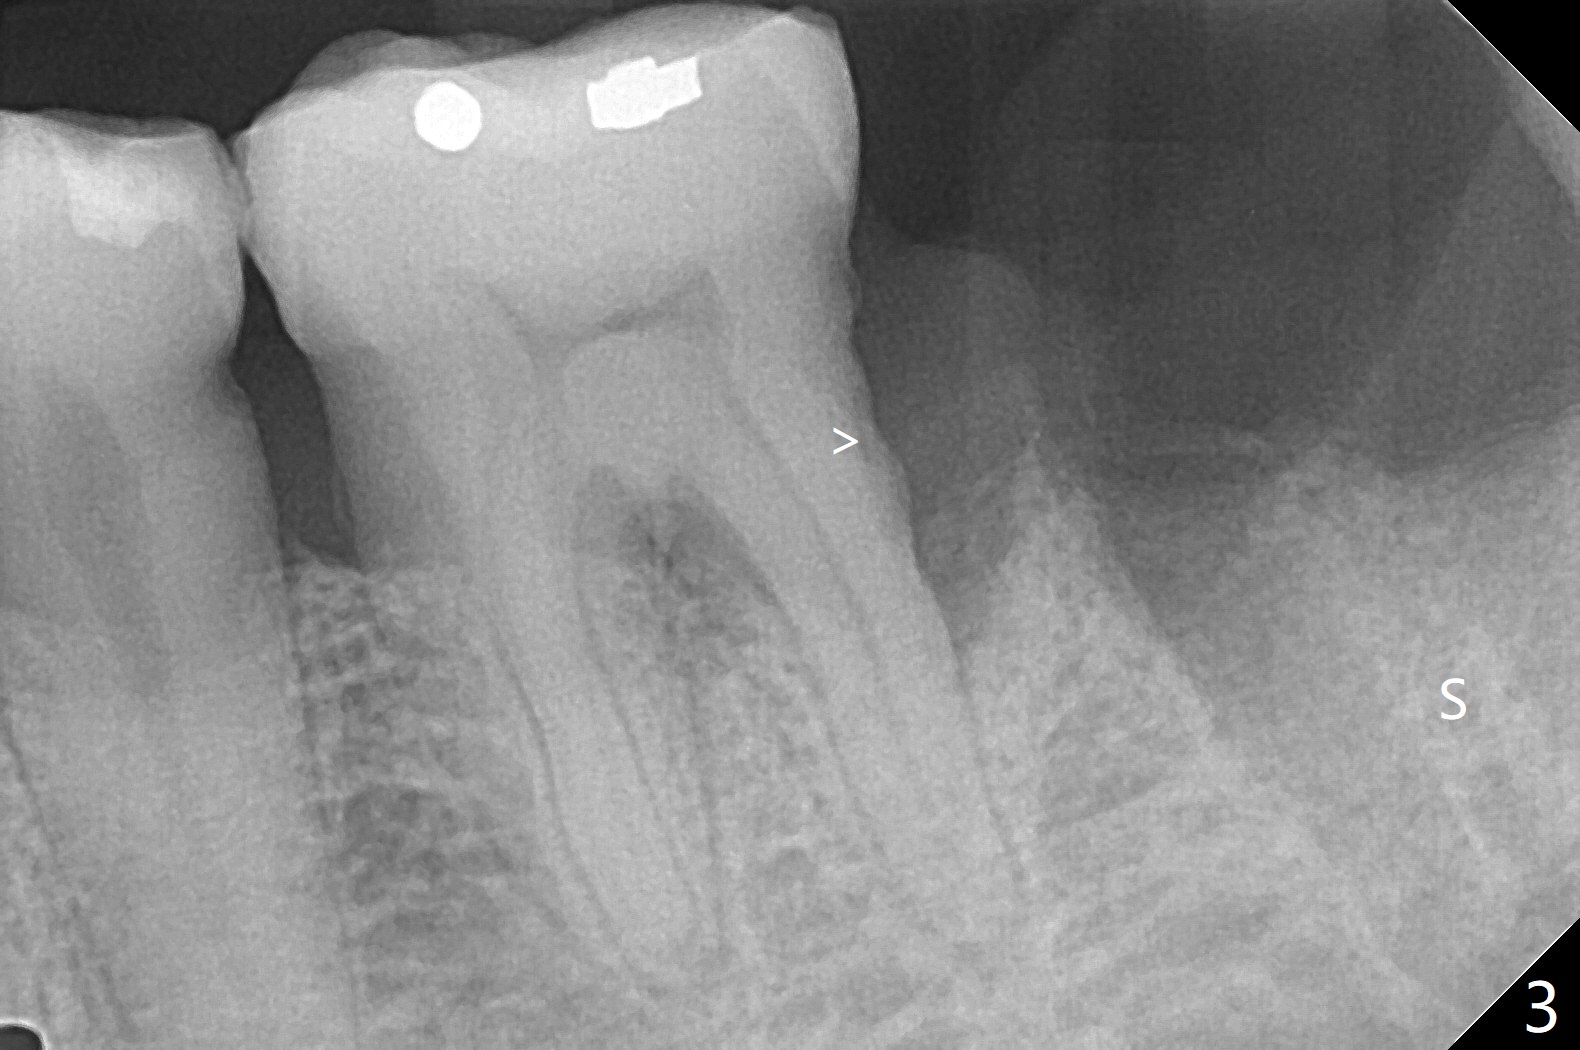

60岁男,吸烟,口腔卫生不好,不积极配合治疗,下前牙两个植体螺纹暴露,但是没有症状。两年中,左下七(图一,二)不能保留(图三),虽然六远中结石被清除(图三>),七位点保留(图四 *)时未能顺便在六远中填入骨粉(用血混合,胎盘膜覆盖)。四五个月后,七种植时将钻头骨粉放置于六远中缺损处,如何才能让骨粉在患处生根发芽?术后一个月,去除树脂敷料后,最表面骨粉未能被整合,下面骨粉好像已经与肉芽组织结合了(图五),其实根尖片应该拍摄证实这一点。吸烟者血供不好,愈合欠佳。术后三个月牙槽嵴宽(图六);高度稍微减低(图七)。术后4个月CT显示近中牙槽窝正好位于缺牙区正中(图八),所以植体必然进入近中窝(图九)。